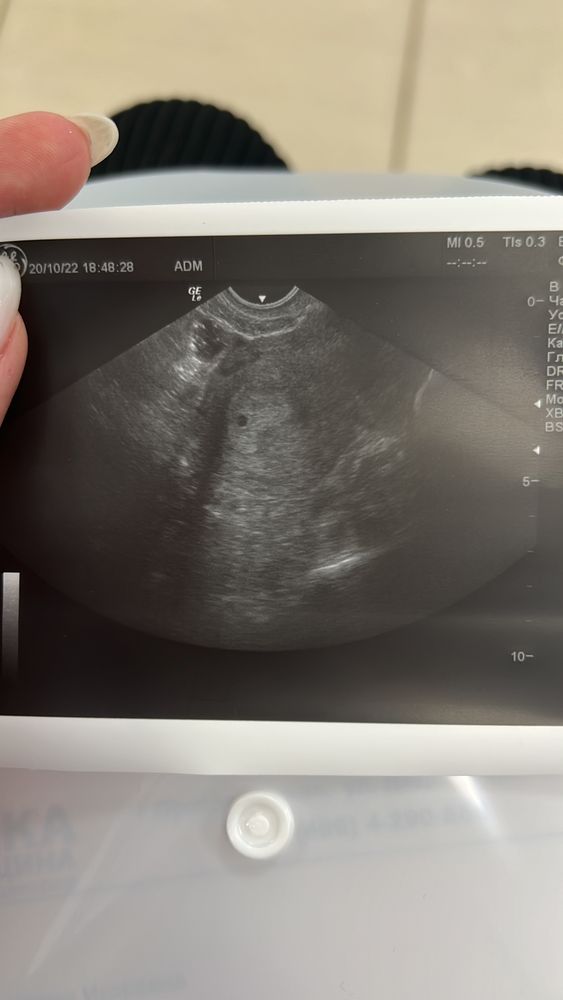

Всем привет ! Сегодня 9 дней задержки , сходила к гинекологу в мед центр , полноценно узи делать она отговорила, предложила на секунду посмотреть чтоб подтвердить 🫶🏼 вообщем сказала беременность маточная , и я выдохнула 🥰 жить стало легче . На 29 число записана к Узисту лучшему в городе , вот теперь думаю чего делать идти или нет 🤔 Гиня сказала через 2 недели все посмотрим и запретила тренировки и рекомендовала половой покой 👉🏻👌🏼